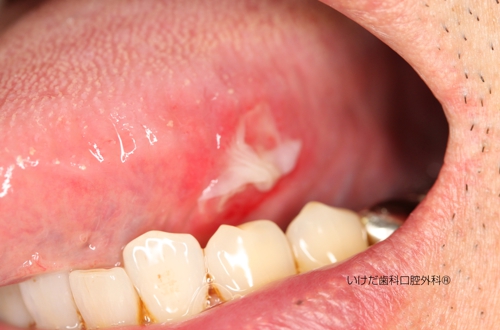

頬粘膜に発生したヘルペス性口内炎

ヘルペスウイルスによる感染。口唇ヘルペスが多いが、口腔内の口蓋、歯肉、咽頭にも発生する。

初期には水疱(水ふくれ)ができ、その後破れ、かさぶたになって治癒する。

口内炎によく似ている。

疲労などによる免疫低下、虫歯や歯石などの刺激による粘膜の傷口からの感染、など。

免疫回復のため休養、ヘルペス用軟膏の塗布、抗ヘルペス剤の服用、含嗽、など